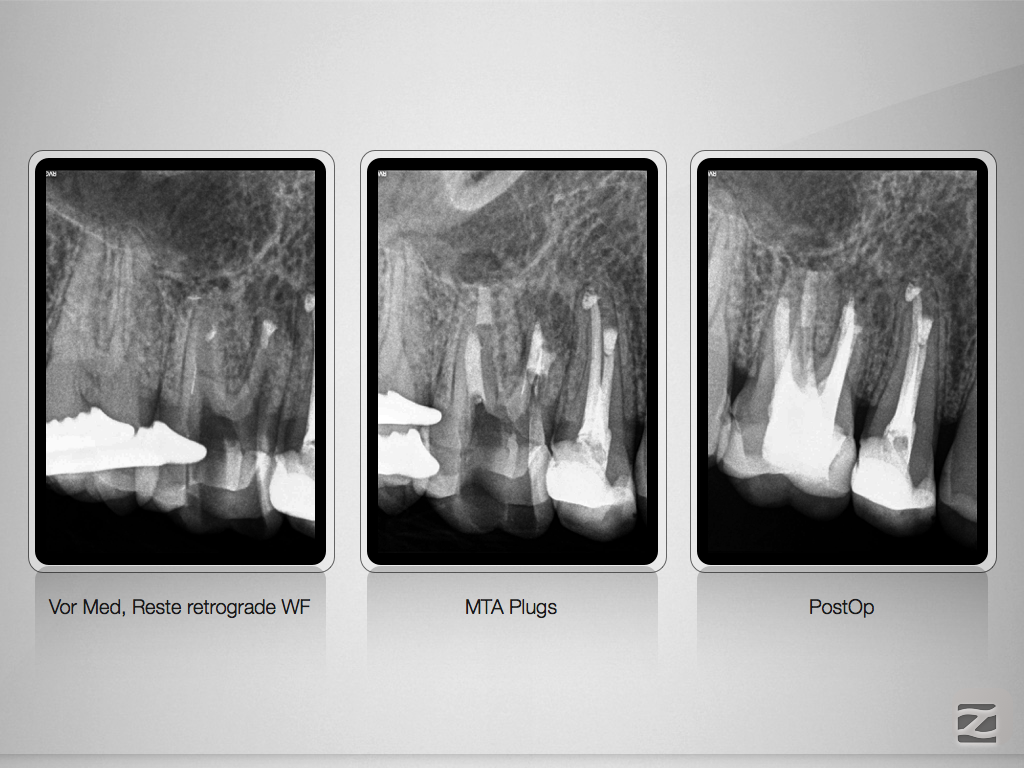

16d-013

Revision nach Resektion